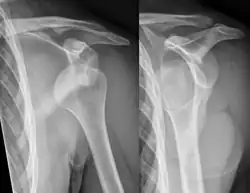

-

Anterior dislocation of the right shoulder. AP X ray -

Anterior dislocation of the right shoulder. Y view X ray.